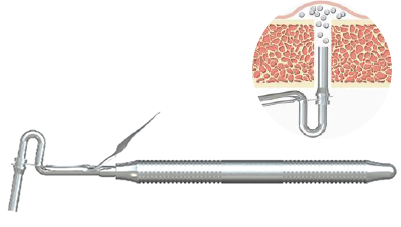

Наконечник для гидросепарации

AQT

Система гидросепарации

AQHST